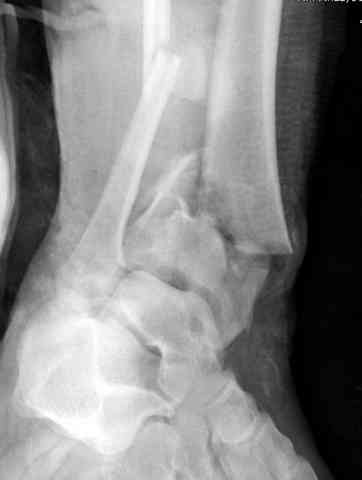

Добавлены КТ снимки. Прошу прощения за качество.

С уважением, Коваленко А.Н.

Снова приветствую вас, коллеги. К моменту вступления в обсуждение аксакалов, операция была, увы, выполнена(31.10.07.) Начали с доступа к наружной лодыжке, произвели ее фиксацию спицами, развернули кусок заднего края, наложили дистрактор, затем произвели дистракцию, фиксацию спицами дистального эпиметафиза б/бк,Рентгено-контроль. синтез наружной лодыжки 1/3пластиной. из двух коротких разрезов сформирован канал под медиальную тибиальную пластину LCP. Края ран ушиты без натяжения. Прочувствовать жесткость фиксации винтами с угловой стабильностью не удалось, поэтому дистрактор оставлен на энное время.

На представленных R-снимках не окончательный вид после остеосинтеза. Дистальная опора давила на стопу, пришлось ее сместить проксимально, в рез-те чего, она закрыла щель сустава, последние снимки не информативны.